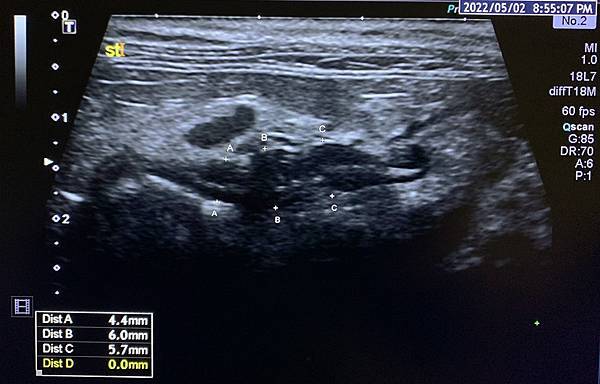

以腹腔超音波評估腫瘤區胃壁和腫大的淋巴結。

(1) 在化療前的基準點,腫瘤區胃壁厚度平均9.3mm,最厚的部分9.5mm。

在最近一次的反應評估,厚度平均4.5mm,最厚6.4mm。

胃壁厚度減少許多,且逐漸看得出原本的分層。

(2) 在化療前的基準點,胃幽門區域的淋巴結14x6mm。在最近一次的反應評估,淋巴結11.2x5.5mm。

總結,病灶區沒有消退回正常的樣子,但恢復許多,臨床症狀的改善幅度大,所以判定對化療的反應理想。

▷ 治療前的胃,可見腫瘤區的胃壁非常厚且分層消失。

▷ 治療後,腫瘤區胃壁和淋巴結都恢復到較接近正常的樣子。